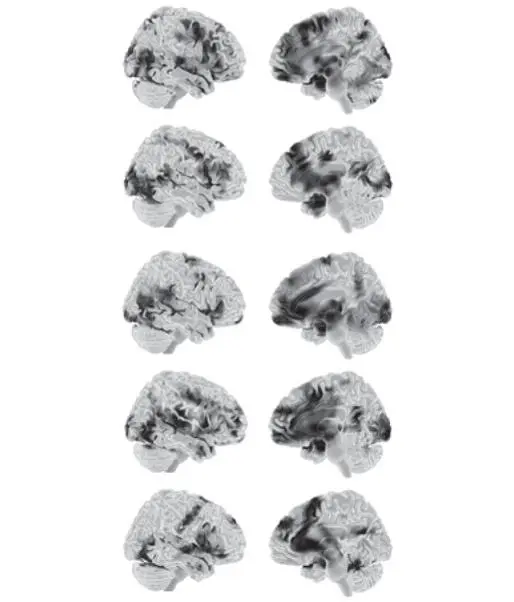

Наш проект с метаанализом продолжается, и к настоящему моменту мы собрали почти четыреста томографических исследований мозга. Для этих данных мы с коллегами применили анализ классификации (глава 1), чтобы создать пять суммарных сводок для категорий эмоций, показанных на рис. Г.2. Во всех пяти случаях значительную роль играет интероцептивная система. Все пять раз также присутствовала управляющая система, но для счастья и печали — менее четко. Помните, что вы здесь смотрите не нейронные «отпечатки», а просто абстрактные сводки. Ни один отдельный случай гнева, отвращения, страха, счастья или печали не выглядит в точности так, как соответствующая сводка. Каждый случай может использовать различные сочетания нейронов, как мы знаем из принципа вырожденности. Для каждого отдельного исследования в метаанализе, скажем, гнева, активность мозга была ближе к сводке для гнева, чем к другим сводкам, поэтому он был идентифицирован как гнев. Соответственно, мы можем диагностировать случай гнева, но мы не можем определить, какие именно нейроны будут активны. Другими словами, мы применили дарвиновский принцип популяционного мышления к конструированию гнева. Тот же самый результат получался для остальных четырех изученных нами категорий эмоций [692].

Рис. Г.2.Статистические сводки для следующих понятий (сверху вниз): «гнев», «отвращение», «страх», «счастье» и «печаль». Это не нейронные «отпечатки» (см. главу 1). Слева вид сбоку, справа — медиальный